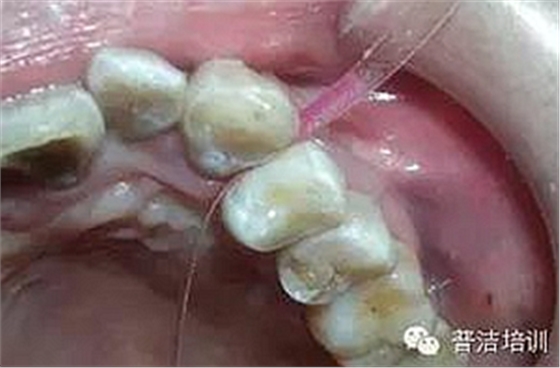

十四、完全就位前去除多余的水門汀,并用牙線和探針仔細去除牙齒之間的多余材料。

牙線去除鄰面樹脂粘結(jié)劑

鄰面拋光